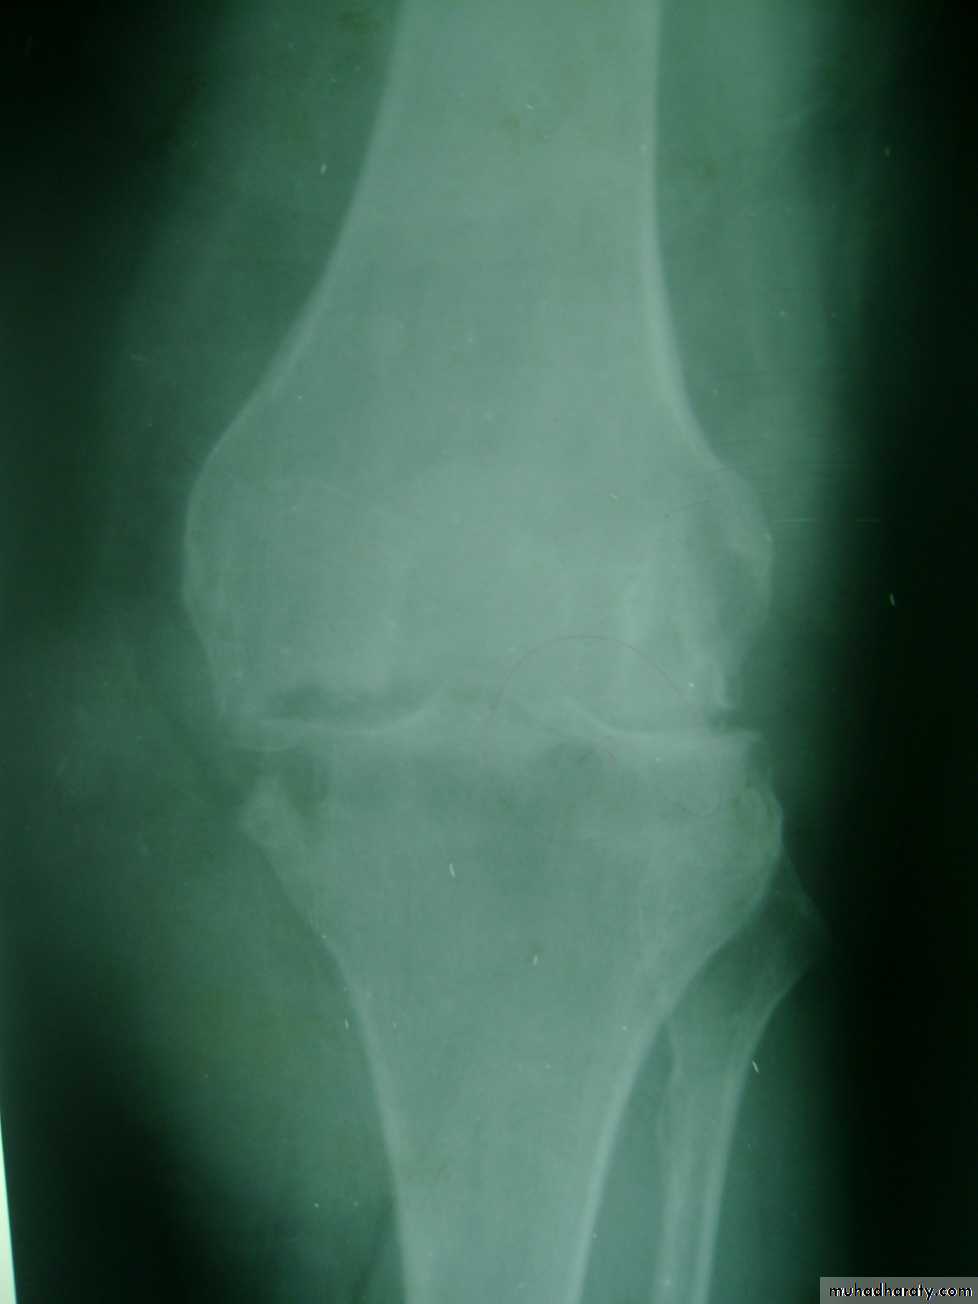

Radiographic features of OA

1- Asymmetric loss of cartilage ( narrowing of joint space).2-Sclerosis of subchondral bone, with subchondral cyst sometimes.

3- Osteophytes (spurring of the joint margins directed toward joint line).